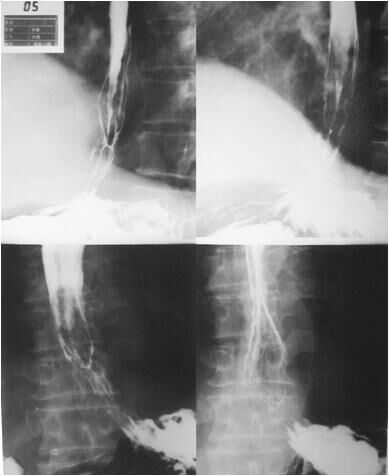

图一:返流性食管炎动态DR造影图像

据四川南部某肛肠专科医院院方透露,动态DR装机一年多以来,已经为1000余名食道、胃、十二指肠、大肠、直肠等的炎症、溃疡、息肉、憩室、肿瘤、癌变等患者做了准确检查和诊断,深受广大患者青睐。其中有一位患腐蚀性食道狭窄的患者说道,吃东西喝水都觉得喉咙灼痛,根本无法通过胃镜检查,幸好有肛肠医院的这台动态DR,不用插管,只需要配合医生进行造影检查,就能及时得到诊断及有效的治疗。

图二:食道良性狭窄(腐蚀性)